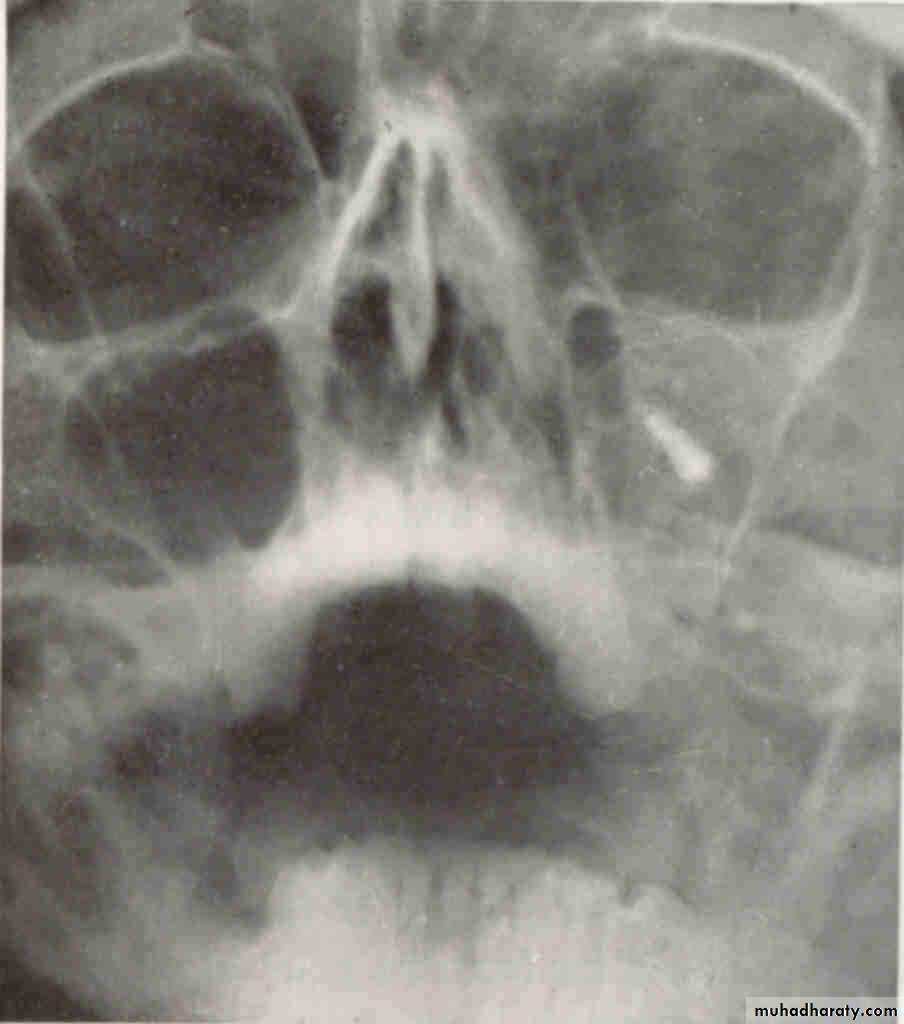

FOREIGN BODYWATERS VIEW(Occipitomental )